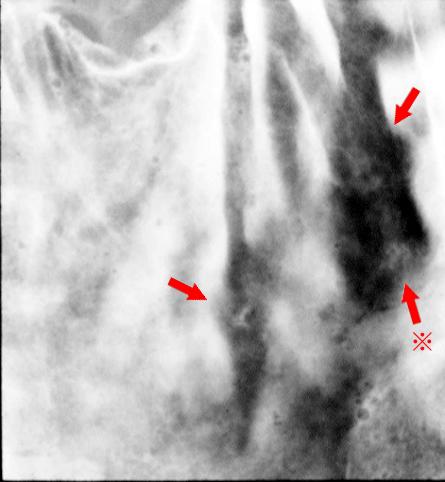

Linfoma Maligno de Estómago que desapareció naturalmente sin el uso de medicamentos anticancerígenos

Linfoma Maligno/Linfoma Maligno tipo MLP

parte(separada por órganos)

estómago(región)/ángulo

método de exámen

Rayos X

diámetro mayor del tumor

1 - 9

múltiples tumores(en un mismo órgano)

presente(simultáneo)

múltiples tumores(en varios órganos)

ausente